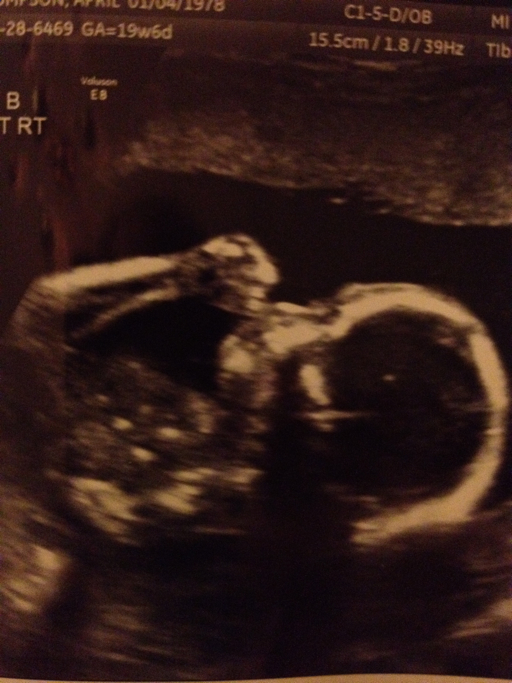

20 week picture:

Anatomy scan went very well.  Both girls are estimated to weigh 11oz and measure 8.5 inches long.  I've been having some contractions but there hasn't been any change in my cervix which is good news.  They'll just be sure to keep an eye on that.  Both babies were very active during the u/s but especially Baby B.  It was a little harder to get her measurements because she just wouldn't be still.  At Taylor's request they checked the genders again.  No surprises!  They have such cute profiles - I can't wait to see them in person!

Baby B: